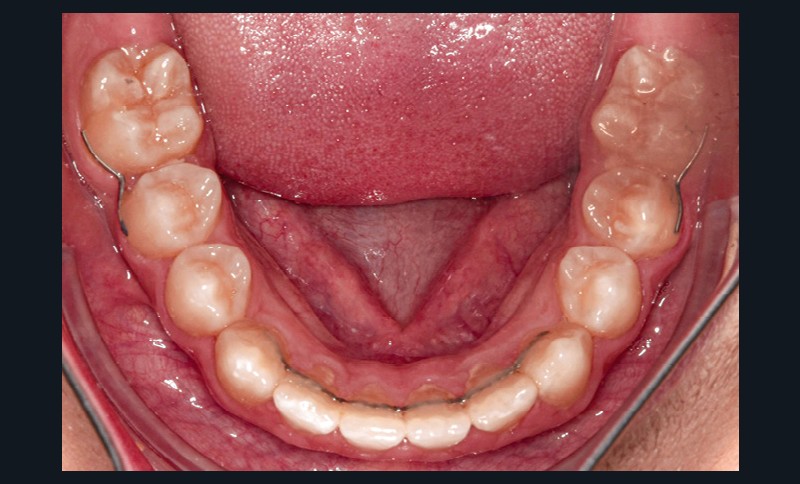

- dysharmonie dento-arcade (DDA) sévère ;

L’extraction de 16, 26, 36, 46 a été réalisée 6 mois avant la pose du multi-attache, permettant une mésialisation spontanée partielle.

La fermeture des espaces résiduels d’extraction a été réalisée par activation de boucles de fermeture sur arcs en acier, avec plicatures préventives des effets parasites (Tip back, Toe in).

Des élastiques intermaxillaires de Classe II (1/4’’, 4 oz) ont renforcé l’ancrage et corrigé la relation sagittale. La mésialisation de 37 et 47 s’est faite progressivement, avec contrôle des axes et de l’inclinaison radiculaire.

En complément des fils de contention 3-3 bimaxillaires, des contentions (fils collés acier 0.16 x0.22) ont été réalisées entre 15-17, 25-27, 35-37 et 45-47. L’objectif était d’éviter une réouverture des espaces post mésialisation.

Une sur-correction de la rotation de 17 aurait été souhaitable pour optimiser l’alignement et les rapports occlusaux (fig. 2a-d).